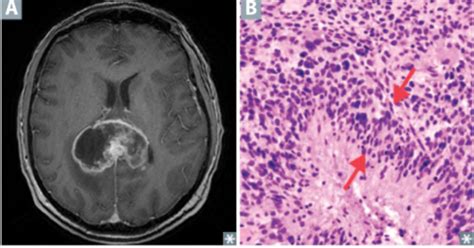

Alright, let’s get a bit more granular and talk about what’s actually happening under that microscope when we see pseudopalisading . Imagine a brain tumor as a bustling, chaotic city. Within this city, there are areas where things are booming and growing rapidly, and other areas where the resources are scarce, leading to the death of cells – these are the areas of necrosis. Pseudopalisading occurs when the tumor cells, in their relentless drive to multiply and spread, start to congregate in the regions surrounding these necrotic zones or along the tiny blood vessels (capillaries) that feed the tumor. It’s like the tumor cells are forming a protective barrier or a staging ground around these critical areas. The ‘pseudo’ part of the word means ‘false,’ and ‘palisading’ refers to a fence-like arrangement. So, ‘pseudopalisading’ means a false fence-like arrangement of tumor cells. They aren’t a true, organized fence, but they look like they are because they are so densely packed and aligned. This unique arrangement is thought to be a response to the harsh microenvironment around the dead tissue. The lack of oxygen and nutrients in the necrotic core might signal to the tumor cells to cluster together, perhaps to share resources, protect themselves, or to prepare for invasion into the healthier, more oxygenated brain tissue nearby. It’s a survival mechanism gone rogue. This pattern is not something you see in benign or slow-growing tumors. It’s a red flag, a siren, screaming ‘aggression!’ The more prominent and extensive the pseudopalisading, generally the more aggressive the tumor is considered to be. This finding is absolutely critical for neuropathologists. When they examine a biopsy, they’re not just identifying that it’s a tumor; they’re grading its severity and predicting its behavior. Pseudopalisading is one of the key features that helps them distinguish between different types of gliomas and guides the subsequent treatment strategy. It’s a visual cue that tells a complex story about the tumor’s biology and its potential to cause harm. So, while it might sound like a minor detail, this microscopic pattern is a cornerstone in the diagnosis and management of aggressive brain cancers.

Now, let’s talk about the star player, or rather, the villain, often associated with pseudopalisading : glioblastoma multiforme (GBM) . Guys, if you hear about pseudopalisading in the context of a brain tumor, GBM is very likely on the table. This is because pseudopalisading is considered one of the hallmark histological features of glioblastoma. What does that mean? It means it’s one of the defining characteristics that pathologists look for when diagnosing GBM. GBM is the most common type of malignant glioma, meaning it’s a primary brain cancer that arises from glial cells (the supportive cells of the brain), and it’s notoriously aggressive. Its hallmark is its rapid growth and its tendency to infiltrate extensively into the surrounding normal brain tissue, making it incredibly difficult to remove completely through surgery. The presence of pseudopalisading in a GBM biopsy is like a flashing neon sign indicating just how aggressive this tumor is. The dense lining up of tumor cells around areas of necrosis and microvascular proliferation (another key GBM feature, where new, abnormal blood vessels form) is a direct visual representation of the tumor’s relentless march. It suggests that the tumor cells are actively responding to their environment, adapting, and seeking out new territory. Think of it as the tumor’s way of regrouping and strategizing its attack. The cells forming the palisades are often in a state of high proliferation, meaning they’re dividing rapidly. This characteristic pattern helps pathologists differentiate GBM from less aggressive gliomas, such as diffuse astrocytomas or oligodendrogliomas, where these features are typically absent or much less pronounced. The implication of finding pseudopalisading in a GBM is significant. It reinforces the understanding that this is a tumor that needs to be treated aggressively and with a multi-modal approach. It tells the medical team that the tumor is likely to recur, even after treatment, and that close monitoring will be essential. So, when you hear about pseudopalisading, it’s almost always in conjunction with the most challenging form of brain cancer, underscoring the severity and the urgent need for effective therapeutic strategies. It’s a critical piece of the puzzle in understanding and fighting glioblastoma.